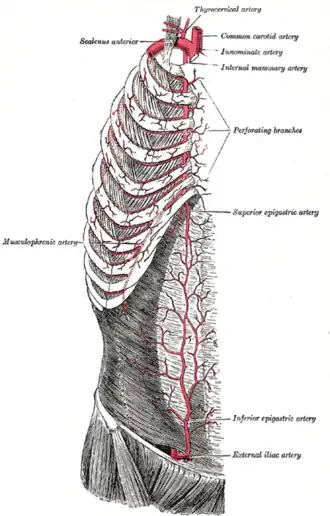

Vasculature entering at top. (Note: internal mammary is now known as internal thoracic artery.)

Vasculature entering at top. (Note: internal mammary is now known as internal thoracic artery.)

The clavicle articulates with the manubrium to form the anterior border of the thoracic outlet. Above the superior thoracic outlet is the root of the neck, and the superior mediastinum is inferiorly related. The brachial plexus is a superolateral relation of the thoracic outlet. The brachial plexus emerges between the anterior and middle scalene muscles, superior to the first rib, and passes obliquely and inferiorly, underneath the clavicle, into the shoulder and then the arm. Impingement of the plexus in the region of the scalenes, ribs, and clavicles is responsible for thoracic outlet syndrome.

Structures that pass through the thoracic inlet include:

- arteries

- left common carotid artery

- left subclavian arteries